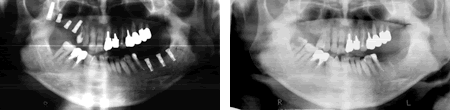

普通、歯科医院で撮影している「レントゲン写真パノラマ」というのがこのような写真です。横面から撮影していますので、平面しか見ることはできません。

では、CTで撮影したものがどう見えるのかご覧下さい。これが普通の医科用CTで撮影した画像です。